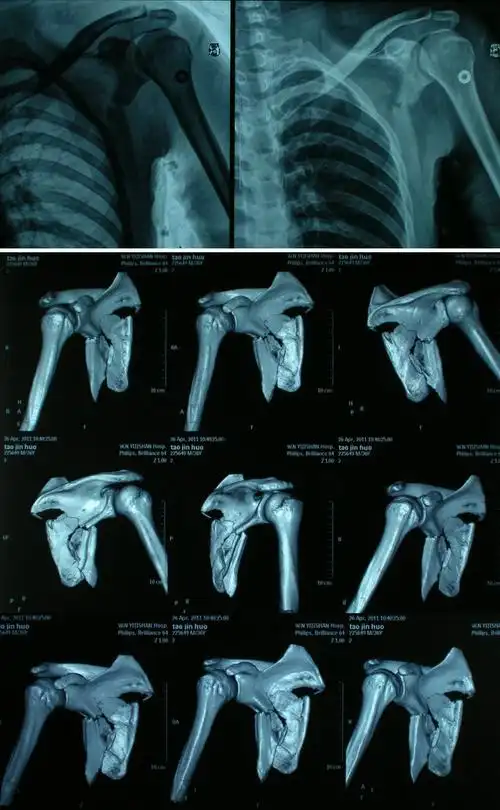

腋路治疗肩胛盂骨折

患者男性,摔伤致右肩关节疼痛,活动受限1天,ct示右肩盂骨折